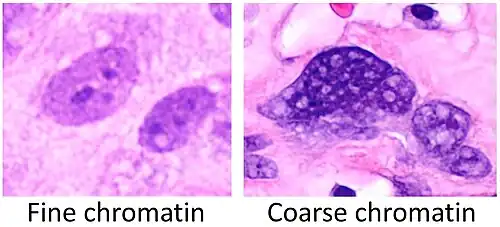

Fine chromatin when inconspicuous (essentially only nucleoli seen in the nuclei), versus coarse chromatin.

Fine chromatin when inconspicuous (essentially only nucleoli seen in the nuclei), versus coarse chromatin. -

Sometimes "heterochromatic" versus "euchromatic" nuclei are used for visual appearance, but this strictly refers to the molecular structure of DNA.

Sometimes "heterochromatic" versus "euchromatic" nuclei are used for visual appearance, but this strictly refers to the molecular structure of DNA. -